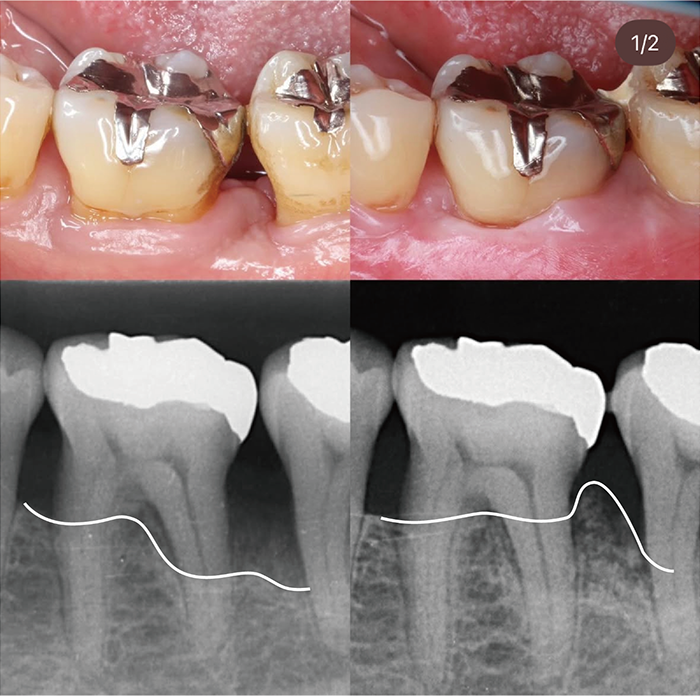

• case01

01のサムネイル